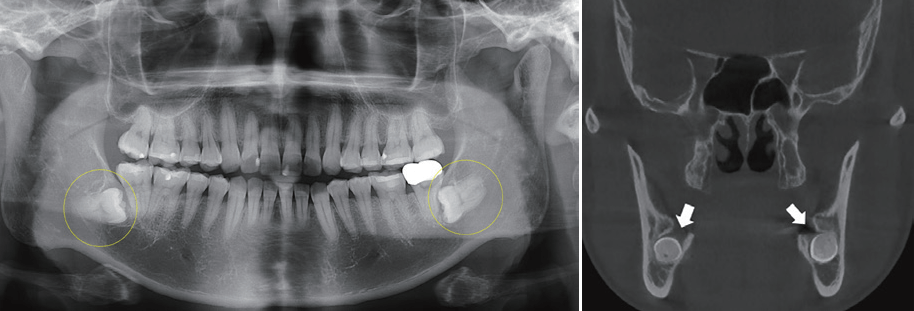

특히 치과에서 자주 촬영하는 2차원적인 파노라마 방사선 사진상에서는 사랑니가 완전히 묻혀 있는 것처럼 보이지만 3차원 컴퓨터 단층촬영 시에는 볼이나 혀 쪽 상방에 뼈가 없는 경우가 있습니다(그림). 이러한 경우 중년에 증상이 발생하여 내원하는 분이 더러 있습니다. 따라서 파노라마 방사선사진에서 사랑니가 완전히 뼈에 묻혀 있는 것으로 관찰되는 경우에도 추적 관찰이 필요할 수 있습니다.

Panoramic view 사랑니발치/ ct 사랑니발치